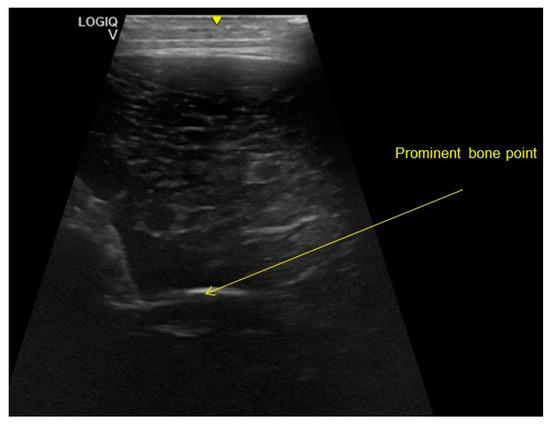

2.2.2. Ultrasound Examination